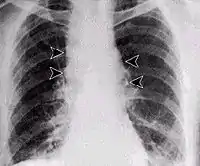

У загальному аналізі крові спостерігають лейкоцитоз, нейтрофільоз, підвищення ШОЕ. При легеневій формі рентгенологічне дослідження легенів або комп'ютерна рентгенівська томографія (КТ) відзначає розширення середостіння, ознаки медіастиніту, однак відсутня інфільтрація легень. При дослідженні ліквору в разі наявності сибіркового менінгіту виявляють помірний нейтрофільний плеоцитоз з домішками вилужених еритроцитів.